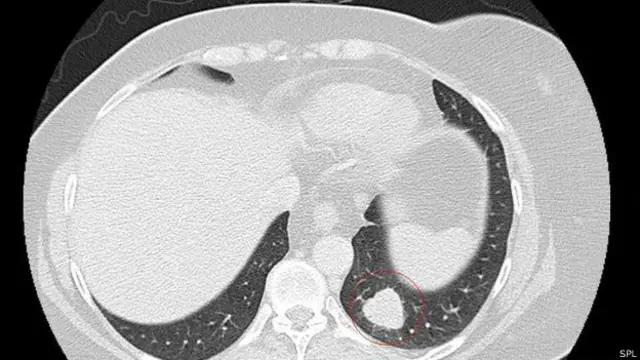

Новообразование на ее лице, которое считалось доброкачественным, оказалось на самом деле меланомой и дало метастазы в легкие. Врачи давали ей 18-24 месяца жизни.